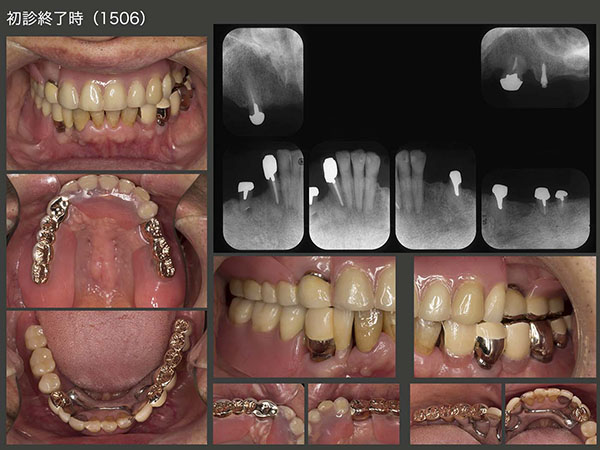

2015年6月,初診終了時の状態.初診より3年2ヵ月が経過してしまった.患者さんには長い間通院してくださり,心より感謝する次第である.上下顎とも支台歯が左右側にあることから,義歯の安定はすこぶるよい.左上のミニインプラントは役目が終わったので本来なら除去すべきところであるが,特に問題もないことからこのまま置いておくことにした.

義歯装着時の状態.通常ならばコーヌス義歯を選択することが多いが,この症例は左上5および右下4が移植歯であるため,流石にあまり側方力をかけたくないと思い,磁性アタッチメントを使用した.左下6の近遠心根は根面板を装着した.

根面アタッチメントを用いるとき,義歯で支台歯を覆ってしまうと,唾液による自浄作用が得られず,根面カリエスが生じやすい.そこで今回は,磁性アタッチメントおよび根面板の上に金属の上部構造体を製作し,支台歯の周囲をすべて開放した.